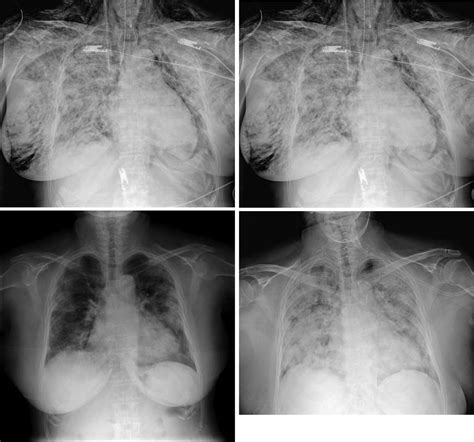

El tratamiento del enfisema subcutáneo se basa en la observación y el control de posibles complicaciones. Este cuadro es potencialmente peligroso en cuanto puede afectar a la permeabilidad de vías respiratorias altas o a planos torácicos y mediastínicos.

En casos raros, si el enfisema afecta la vía aérea o el mediastino, puede ser necesario un tratamiento más invasivo, como la descompresión quirúrgica.

| Diagnóstico | Historia clínica detallada, palpación para detectar crepitación, radiografías. |